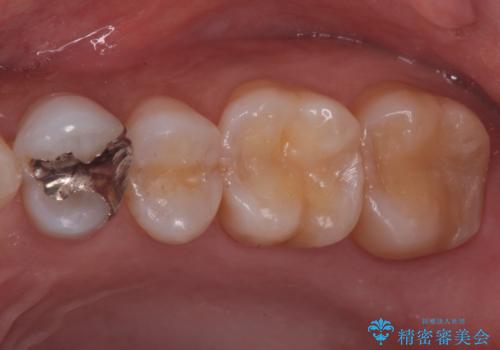

- 前歯を綺麗にしたいとのことで来院されました。

色調・適合ともに改善するために一度被せ物を外し、歯の形を整えた後に新しい被せ物を装着していきます。

歯ぐきの炎症を抑えつつ、被せ物と歯との境目がわからなくなるよう被せ物を装着しました。

審美性が大変改善されたことで患者様にもご満足いただけました。